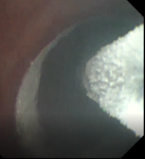

基于以上发现,此次在上海申康医院发展中心重大临床研究项目支持下,团队进一步研究发现通过冷冻治疗设备控制,冷冻时设备将液氮输送至导管冷冻端,使冷冻端表面温度骤降,吸收环境温度,组织结冰,杀死病变组织细胞。解冻时,设备将常温氮气输送至导管冷冻端,使组织温度升高,进一步破坏病变组织细胞,达到治疗目的。

接受新疗法的患者两年前就明确诊断为慢阻肺,之后长期吸入大剂量信必可治疗,但咳痰和气急的症状仍控制不佳,本次入院复查发现肺功能明显下降,为中度阻塞性通气功能障碍。4月15日,王昌惠主任、李萍主任医师和李譞主治医师运用冷冻喷雾技术,成功完成COPD患者的支气管粘膜消融手术,术后患者无不良反应发生,第二天即顺利出院。症状得到明显改善,患者对王昌惠教授团队的感激之情溢于言表。

王昌惠教授表示,纤毛功能障碍、黏液高分泌、细菌定植增加、气道炎症与氧化应激等均为慢阻肺发病的重要机制,近几年随着支气管镜介入技术的不断进步, 非药物治疗方式的液氮计量冷冻喷雾成为研究热点。团队的研究和实践均提示,冷冻喷雾消融治疗可以促进支气管粘膜上皮再生,减少杯状细胞的数量,改善纤毛的运动,进而提高COPD患者的生活质量,同时冷冻治疗具有并发症少、恢复快、不易形成瘢痕组织导致气道狭窄等优势,是COPD患者治疗的新希望,也是团队今后继续努力探索的方向。

术前支气管 术中改变 术后支气管